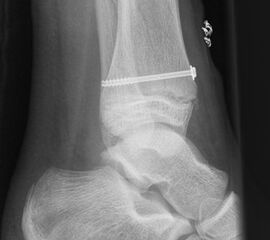

Syndesmosenverletzungen

Relevante, rein ligamentäre Syndesmosenverletzungen sind im Kindesalter extrem selten und den Autoren in der persönlichen Erfahrung nicht bekannt. Die Diagnose einer derartigen Verletzung könnte allein über ein MRT gestellt werden; bei Instabilität müsste dann offen revidiert und die Heilung der adaptierten Bandreste mit einer Stellschraube für 8 Wochen gesichert werden, ergänzt durch eine 6-wöchige Ruhigstellung mit US-Gips unter Entlastung.

Die häufig nicht dislozierten knöchernen Ausrisse können konservativ behandelt werden. Dislozierte Fragmente sollten operativ mit Kirschner-Drähten oder Schrauben fixiert werden (Abb. 32). Die Nachbehandlung umfasst eine 4-wöchige Entlastung im US-Gips. Eine Röntgenkontrolle erfolgt nach Gipsabnahme. Freies Gehen sollte nach 6 Wochen möglich sein. Danach ist auch eine sportliche Belastung des Sprunggelenks möglich (v. Laer 2013).

Eingebrachtes Osteosynthesematerial sollte vor der Vollbelastung entfernt werden.